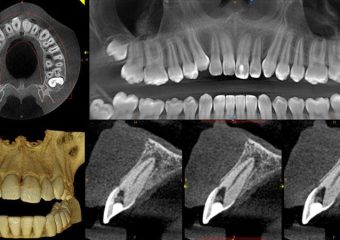

تفاوت اسکن CBCT و عکسبرداری پانوراما

بررسی تفاوت اسکن CBCT و عکسبرداری پانوراما

در این نوشته از سایت دکتر ندا مکانیک بهترین ایمپلنت اصفهان تفاوت اسکن CBCT و عکسبرداری پانوراما را مورد بررسی قرار خواهیم داد.

اسکن CBCT

CBCT مخفف توموگرافی کامپیوتری با پرتو مخروطی است که توسط متخصصان دندانپزشکی استفاده میشوند. این سیستم به دور شما میچرخند و با استفاده از اشعه ایکس مخروطی شکل وضعیت دهان و دندان یا سایر دادهها را ضبط میکنند.

با کمک عکس برداری CBCT در کمتر از یک دقیقه، حدود 150-200 تصویر از زوایای مختلف گرفته می شود. داده های گرفته شده برای بازسازی یک تصویر سه بعدی از قسمت های مختلف بدن شما همچون دندان ها، دهان، فک و گردن، گوش، حلق و بینی (ENT)گرفته می شود.

FMX یا PANO

احتمالاً قبلاً در مورد اشعه ایکس کامل دهان (FMX) یا اشعه ایکس پانورامیک (PANO) از دندانپزشک خود شنیده اید. FMXمعمولاً هر 3-5 سال توسط دندانپزشک شما توصیه شده و تصاویری از هر دندان و ساختارهای اطراف آن را در بردارد. این فناوری برای تشخیص بیماری لثه، حفره ها، آبسه های دندانی و ضایعات استفاده می شود.

همچنین از فناوری PANO می تواند یک تصویر منفرد که اغلب توسط جراحان دهان و ارتودنتیست ها استفاده می شود برای تشخیص سطحی بیماری های دهان و دندان استفاده کرد. این نوع اشعه ایکس جزئیات واضحی را ارائه نمی دهد بنابراین نمی توان برای تشخیص و بررسی های عمق تر و دقیق تر به آن تکیه نمود.

در مقایسه با این اشعه ایکس استاندارد، اسکن CBCT دندان روشی بسیار دقیق تر و موثرتر برای گرفتن اطلاعات در مورد سلامت دندان شما است. فناوری CBCT همچنین از تشعشعات کمتری استفاده می کند که برای دیدن نماها و زوایای مختلف دهان به اسکن کمتری نیاز دارد. به علاوه، برخلاف اشعه ایکس سنتی دندان، سی تی اسکن پرتو مخروطی می تواند هم استخوان ها و هم بافت های نرم را نشان دهد.